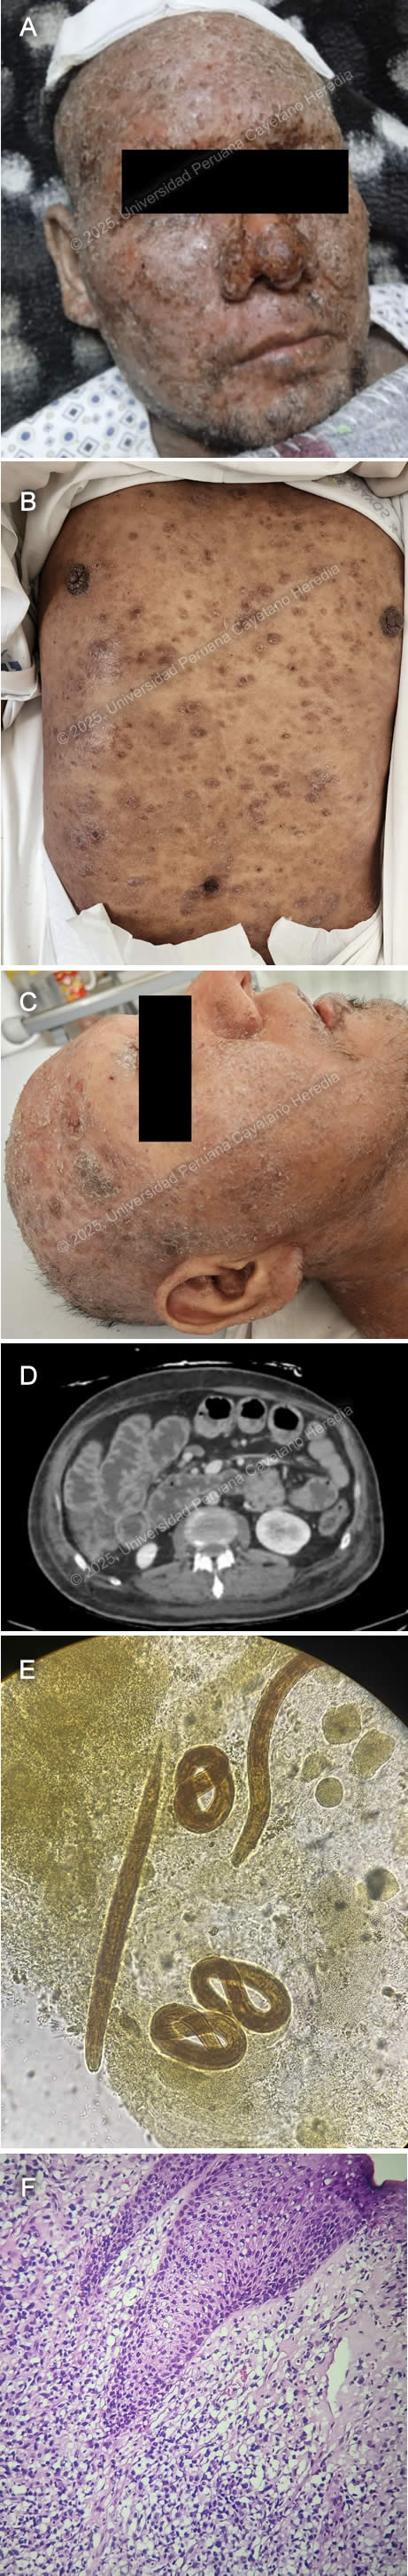

![]() History: A 54-year-old man presents with a six-month history of progressively worsening generalized pruritic skin lesions that initially appeared as hives and papules, affecting the abdomen and upper limbs before spreading to the rest of the body. Three months later, he began experiencing sporadic nosebleeds and increasing numbness in his hands and feet. Due to decreased sensation in his hands, he has developed wounds from unnoticed trauma. In the last month, as his difficulty performing work-related activities worsened, he was advised to seek further medical evaluation. Over the past six months, the patient reports a weight loss of approximately 4 kg without trying. Epidemiology: The patient was born in a rural area of Yurimaguas, in the low jungle of Peru, and has been living in Lima for the past 16 years. He is currently a warehouse worker in Lima. When he was in the jungle, he worked as a farmer for 6 years, cultivating corn, rice, bananas, and cassava, and raising animals including pigs, chickens, and cattle. He reports a past history of cutaneous leishmaniasis at age 12, with complete antimonial treatment. He also mentions having a nasal septum perforation since he was 18, with no clear cause. He denies sick contacts. Physical examination: His vital signs were HR: 78 beats per minute, RR: 18 breaths per minute, BP: 110/70 mmHg, T: 36.7°C, SatO2: 98% on room air. Skin examination revealed multiple very superficial papules and nodules in a dispersed pattern involving his face, abdomen, back, and both upper and lower limbs (Images A, B, C, D). These were associated with nerve thickening (Image E), corneal anesthesia with absence of corneal reflex (Image F), and decreased sensation in the hands and feet. A perforated septum was also observed. The rest of the exam was unremarkable. Laboratory: Initial tests showed hemoglobin at 13.2 g/dL and leukocytes at 5530, with 68.9% neutrophils, 22.2% lymphocytes, 0.2% basophils, 7.6% monocytes, and 1.1% eosinophils. Platelet count was 437000. Liver function tests revealed AST at 17 U/L (normal range 8 to 48 U/L) and ALT at 10 U/L (Normal range 7 to 55 U/L). Total bilirubin was 0.75, with direct bilirubin at 0.3. Renal function was within normal limits, with urea at 21 mg/dL and creatinine at 1.02 mg/dL. Glucose was 68 mg/dL. UPCH Case Editors: Carlos Seas, Course Director / Paola Nakazaki, Associate Coordinator |

![]() ![]() Discussion: A skin punch biopsy from the lesions on the back was performed, revealing a moderate inflammatory infiltrate in the dermis with a nodular and linear pattern. It consisted of vacuolated histiocytes containing multiple bacillary structures. Fite–Faraco staining (Image G) is positive (3+), confirming the diagnosis of lepromatous leprosy. Leprosy is a chronic granulomatous infection caused by Mycobacterium leprae. It remains a neglected tropical disease present in over 120 countries, with approximately 200,000 new cases each year. Although it was declared eliminated as a global public health problem by 2000, new cases still appear in countries like Brazil, India, and Indonesia, while many nations now report few or no cases (1). In Peru, leprosy is endemic in Amazon regions, especially in the departments of Ucayali, Loreto, Amazonas, Huánuco, and San Martín (2). Twenty six new cases were reported in 2023, all of them from the departments of Loreto and Ucayali (3). Transmission is unclear, though it is thought to occur via respiratory droplets from the nose and mouth of untreated individuals during prolonged close contact (1,4). The incubation period is variable, from months to years, and it commonly affects peripheral nerves, skin, and mucosa (4,5). And if left untreated, it can lead to severe disability, mostly secondary to impairment of nerve function or visible deformity. Clinical manifestations vary among patients due to differences in individual immune responses, and they are classified into Tuberculoid (TT), Lepromatous (LL), Borderline Lepromatous (BL), Mid Borderline (BB), and Borderline Tuberculoid (BT) (6). Lepromatous leprosy is linked to a Th2-dominant immune response to the pathogen and typically presents with widespread, diffuse infiltration of the skin and very superficial papules and nodules (lepromas) containing numerous organisms, along with nerve involvement (5). Diagnosis is made through clinical history and examination, with slit-skin smear microscopy or biopsy with histopathology as needed. Diagnosis requires at least one of the following criteria: sensory loss in skin lesions, thickened peripheral nerves, or detection of acid-fast bacilli on slit-skin smears (7). The absence of reliable point-of-care tests often contributes to delayed diagnosis and increased risk of nerve damage and disability (1,5). WHO guidelines for treatment recommend a three-drug regimen with rifampicin, dapsone, and clofazimine with variable duration depending on the clinical category of presentation, with a recommended 12-month regimen for multibacillary leprosy (1). Monthly RMM is the standard in the US and in countries where clofazimine cannot be obtained (8). Our patient has multibacillary lepromatous leprosy and was started on rifampicin, dapsone, and clofazimine. He is currently undergoing his second month of treatment with no adverse events (Images H, I). Complications can persist even after bacteriological cure and include immune reactions, nerve damage, ocular sequelae, and disabilities. Management is not limited to medication, it also needs long-term support to address the physical, psychological, and social impacts of the disease (9). We would like to thank Dr. David Freedman for his contributions. References |